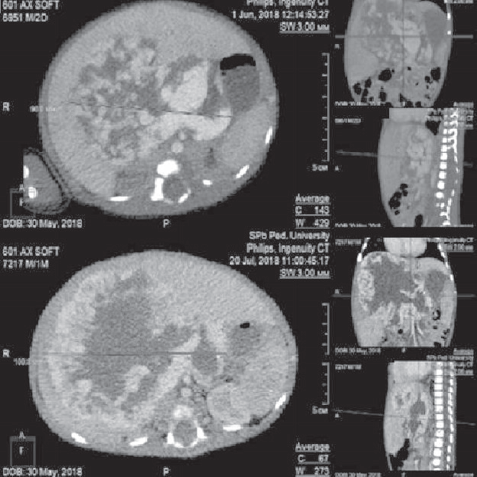

Проведено комплексное обследование: УЗИ органов брюшной полости (июнь 2019 г.) — в правой доле печени визуализируется объемное образование с неоднородной структурой, занимающее большую часть правой доли, с четкими границами и гиперэхогенными включениями. МСКТ с контрастным усилением (июнь 2019 г.) — КТ-картина образования, наиболее соответствующего сосудистому образованию — гемангиоме печени (рис. 4, 5).

Рис. 4. Компьютерная томограмма: объемное изображение васкуляризации образования

Fig. 4. CT: Image of tumor vascularization

Рис. 5. Компьютерная томограмма: фронтальный снимок образования (гемангиомы) печени в артериальную фазу контрастирования

Fig. 5. Frontal CT scan of the tumor (hemangioma) in the arterial phase

МСКТ грудной, брюшной полостей, головы (сентябрь 2019 г.): гигантское образование брюшной полости, увеличение размеров: с 8 × 10 до 16 × 15 см, занимающее бóльшую часть брюшной полости, предположительно сосудистого характера. Отмечается уменьшение просвета брюшного отдела аорты ниже образования, сужение просветов подвздошных сосудов.

По данным контрольного МСКТ брюшной полости с контрастным усилением (ноябрь 2019 г. — возраст ребенка 5 мес.): образование уменьшилось в размерах по всем измерениям, общий его объем уменьшился на 32 %.

МСКТ брюшной полости с в/в контрастным усилением (возраст 8 мес.) — уменьшение образования на 54 %.